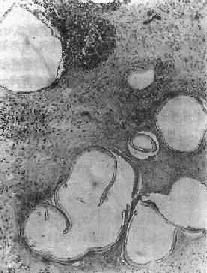

图19-20 肝泡状棘球蚴病 可见多数大小不等的小囊泡,仅见角皮层而不见生发层,囊内无头节,囊泡间组织呈凝固性坏死 肺泡球蚴病少见,多数由肝经血流迁徙而来,或由肝直接蔓延而来。泡状蚴穿出血管后,先在细支气管寄生,引起增生性炎及血管内膜炎。病变也可呈肿块状,类似肿瘤。